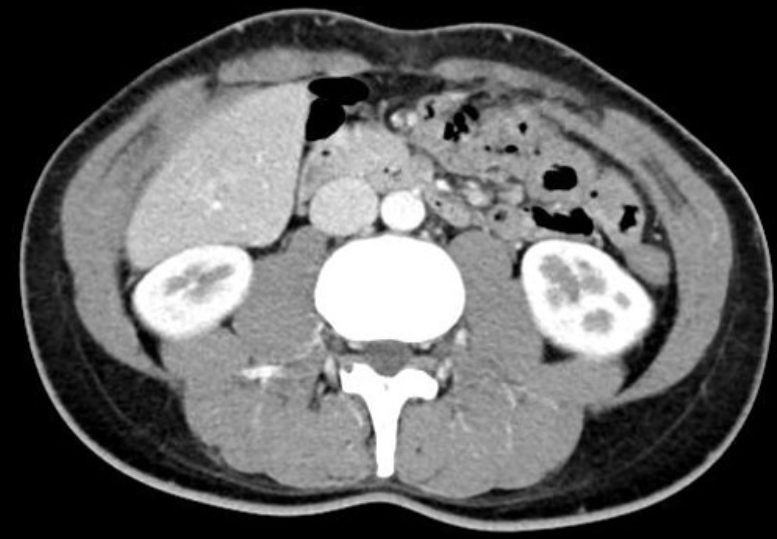

22세 여성이 지난 2주 동안 지속된 식욕 부진과 체중 감소를 호소하며 병원을 찾았다. 최근 4개월 동안 체중이 약 8kg 감소했다. 복부 CT 사진이다. 이 환자의 증상과 관련이 있는 혈관은?

Imp: 상장간막동맥 증후군(SMA syndrome)

급격한 체중감량 과거력과 aorta와 SMA 사이에 duodenum 3rd part가 끼어 있는 CT 소견을 통해 SMA syndrome으로 진단할 수 있다.